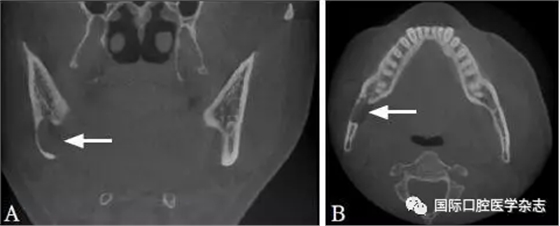

3.4 Stafne骨腔

Stafne骨腔又稱下頜舌側(cè)骨缺損或下頜骨發(fā)育缺損,由Stafne在1942年首次報(bào)道,通常是拍片偶然發(fā)現(xiàn),大多認(rèn)為是下頜骨舌側(cè)皮質(zhì)骨受頜下腺壓迫所致。X線片典型表現(xiàn):與牙無關(guān)的透射影,通常位于下頜神經(jīng)管下方,第一磨牙與下頜角之間的部位(圖10)。當(dāng)其發(fā)生在下頜骨前份且與牙根接觸緊密時(shí)可能混淆診斷[32-33]。通過CBCT顯示下頜骨舌側(cè)骨質(zhì)缺損結(jié)合磁共振成像比較病變組織與唾液腺的信號(hào)強(qiáng)度進(jìn)行診斷,可避免不必要的手術(shù),一般認(rèn)為不需要干預(yù)。

A:冠狀位;B:水平位。

圖 10 Stafne骨腔的CBCT圖像

Fig 10 CBCT of Stafne’ bonecavity